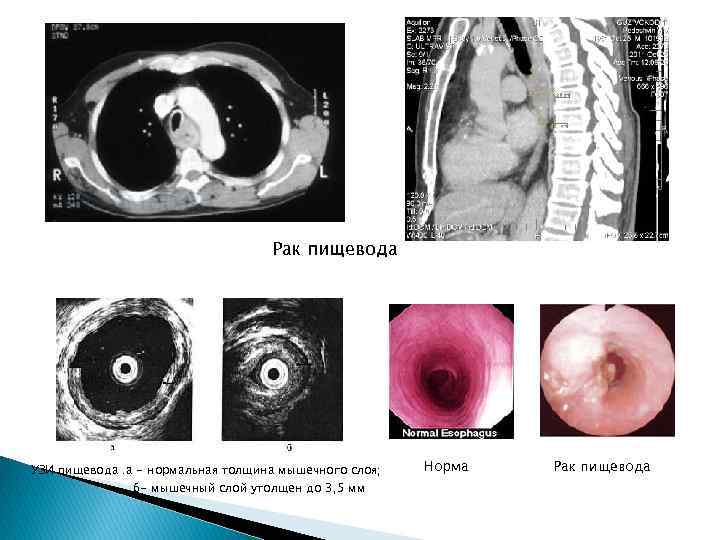

Рак пищевода УЗИ пищевода. а - нормальная толщина мышечного слоя; б- мышечный слой утолщен до 3, 5 мм Норма Рак пищевода